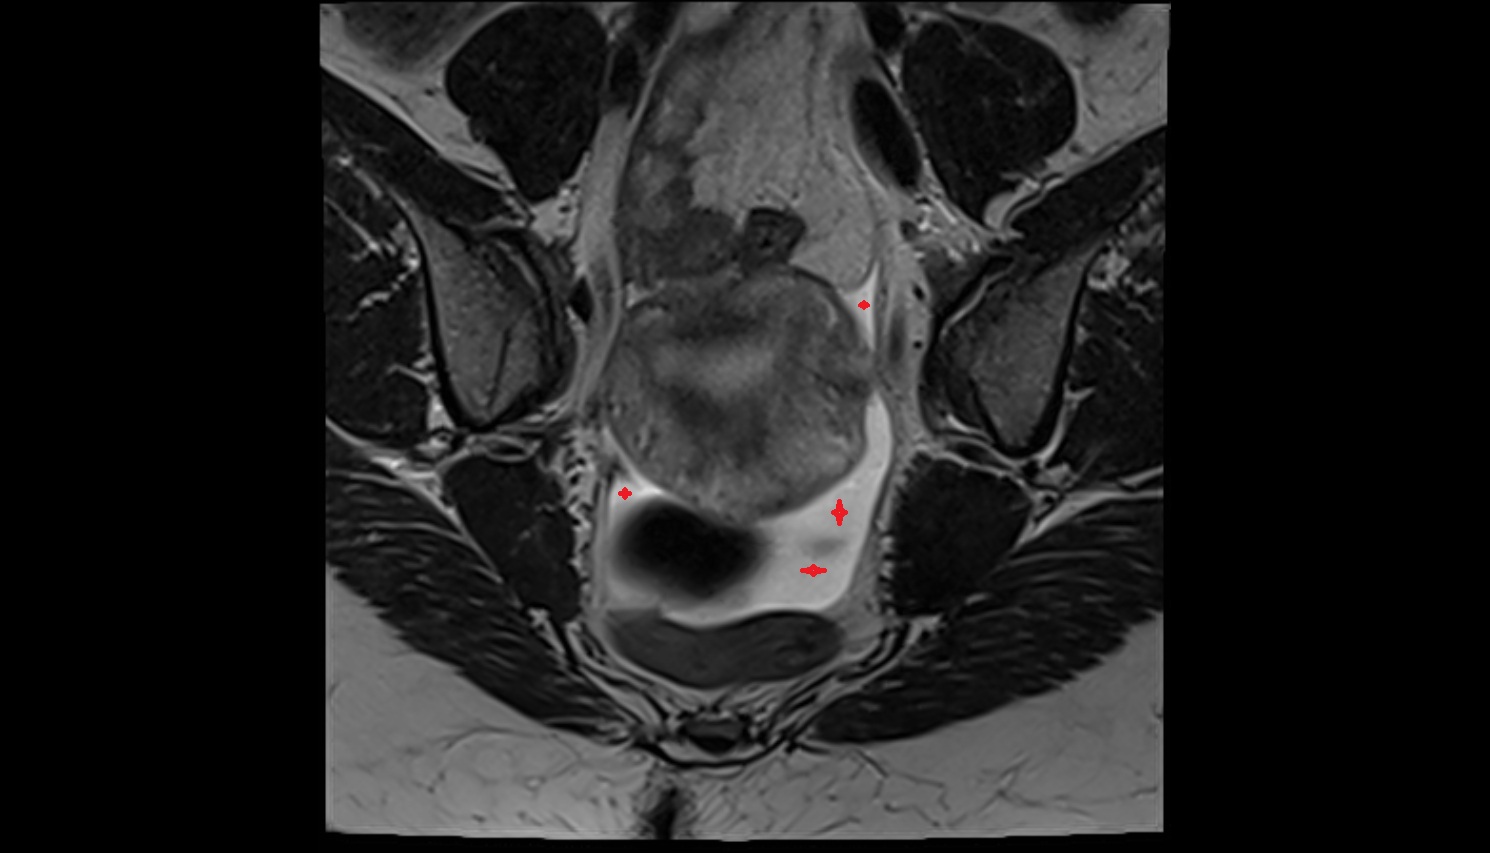

- Uterus

- Body of uterus

- Fundus of uterus

- Cervix of uterus

- Isthmus of uterus

- Vagina

- Endometrium of uterus

- Myometrium of uterus

- Perimetrium of uterus

- Junctional zone of uterus

- Ovaries

- Peripheral zone of prostate

- Anterior Fibromuscular Stroma of prostate

- Central zone of prostate

- Transitional zone of prostate